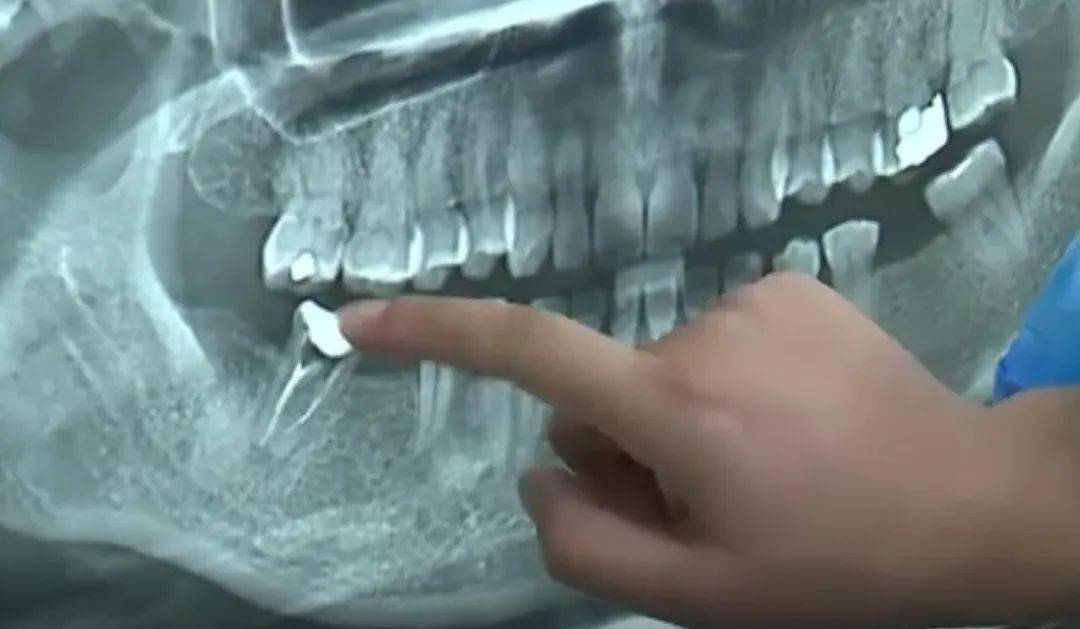

根管断针

对取根管内断针的一点经验